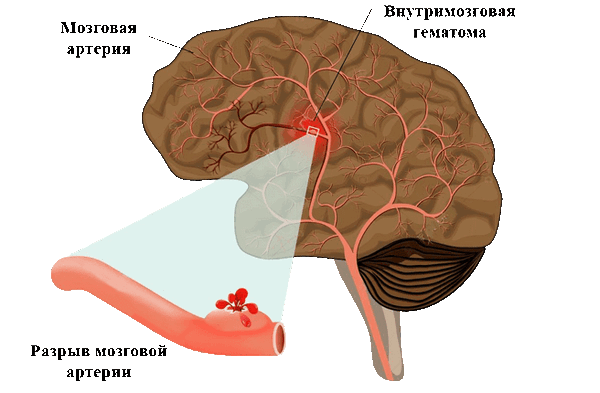

Геморрагический инсульт.

Развитие геморрагического инсульта чаще всего обусловлено гипертонической болезнью на фоне атеросклероза. В некоторых случаях причиной кровоизлияний может быть патология судов (врожденные ангиомы, аневризмы сосудов), а также другие причины артериальной гипертензии (феохромацитома, заболевания почек, СКВ, аденома гипофиза и др.).

происходит пропитывание плазмой крови стенки сосуда с нарушением ее трофики и последующей деструкцией, формированием микроаневризм, разрывами сосудов и выходом свободной крови в вещество головного мозга, т.е. развитие инсульта по типу гематомы. Кроме того возможно формирование инсульта по типу геморрагического пропитывания, в основе которого лежит механизм диапедеза.

В случаях кровоизлияний в мозг, обусловленных разрывом сосуда, зачастую происходит прорыв крови в желудочки мозга или субарахноидальное пространство.

Нередко крупный геморрагический инсульт сопровождается выраженным отеком, что приводит к смещению срединных структур головного мозга, различным типам вклинения, деформациям ствола мозга с последующим развитием вторичных мелких кровоизлияний.